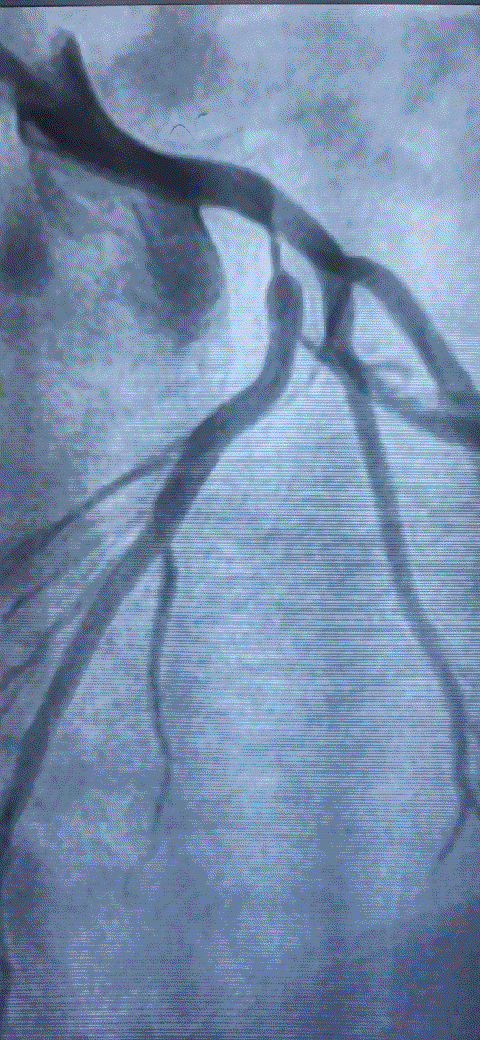

How do you explain this ? 99% occlusion still TIMI 3 flow ?

A. It could be a parallax error. Lesion may not be tight. Should be seen in other views.

B . Forcible Injection by the operator, make it an artificial TIMI -3 flow.

C .Such flows are very much possible .It Indicates a healthy distal micro-circulation a vascular bed in a fully dilated mode.

D. TIMI flow is not reliable here . We need TIMI frame count to confirm.

Follow up questions

1.How much will be the FFR ?

Likely to be less than . 8 definitely , but surprises can happpen

2.Can he be asymptomatic ?

Unlikely.

Final message

Coronary occlusions are ominpresent . While we have mastered the art of successfully taming these anatomical enemies , we are still very much ignorant what these lesions actually do, to the physiology, inspite of half a dozen flow reserve Indices we have.(FFR,iFR, rFR,qFR, dP/dT ,etc)

The question is, at what level of obstruction, it really limits the coronary bllod flow significantly ( both at rest and exertion) . One thing is clear , it is higly variable & Individualistic, the secrets of which lies deep, in the domain of invisible micro-vascular network integrity.

Counterpoint

TIMI flows may no longer be valid in non-ACS situations. The name TIMI , by itself carries flow after thrombolysis. For some unexplained (& debatable ) reasons, we are used to apply this flow grade , in every angiographic flow scenerios irrespective of underlying clinical entity.